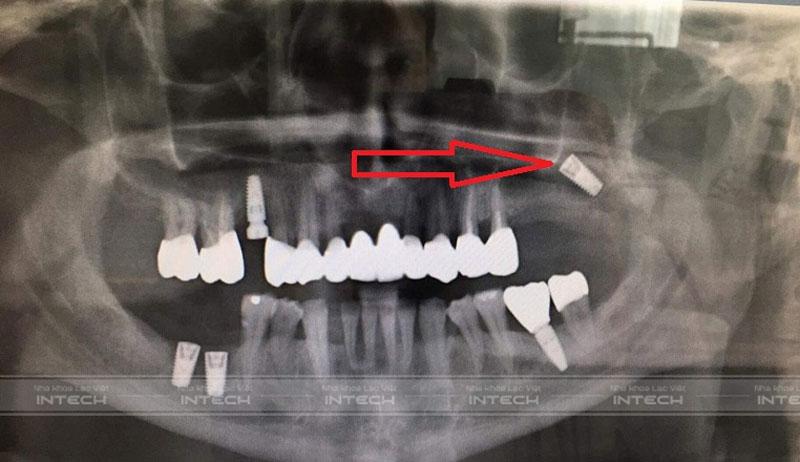

Trụ Implant cắm lệch vào chân răng bên cạnh

Trụ Implant bị cắm sai lệch, xiêu vẹo hoặc xâm lấn vào chân răng bên cạnh có thể dẫn đến nguy cơ tổn thương hoặc chết tủy răng. Ngoài ra, trụ Implant bị cắm sai lệch còn khiến cho phục hình bên trên không sát khít, dễ bị lung lay và dắt thức ăn gây bong sút phục hình. Tệ hơn nữa là vỡ cổ Implant và khi đó sẽ phải khoét bỏ xương để lấy trụ Implant ra ngoài.